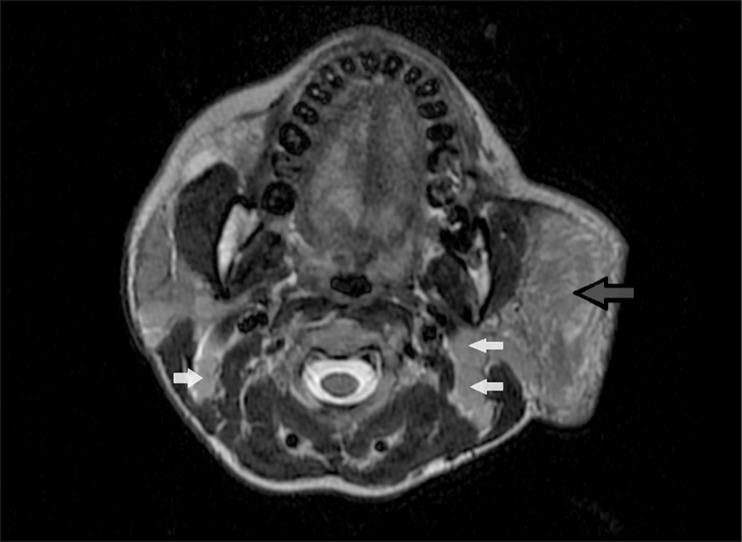

A middle-aged female patient presenting with a history of multiple chronic neck swellings was thoroughly evaluated by ultrasound (US), computed tomography (CT), and magnetic resonance imaging (MRI). The imaging findings included gross enlargement of the left parotid gland, a focal lesion in the right parotid gland, and cervical lymphadenopathy. These features correlated with histopathological findings, and the diagnosis of Kimura disease was made.

一名有多处慢性颈部肿胀病史的中年女性患者接受了超声(US)、计算机断层扫描(CT)和磁共振成像(MRI)的全面评估。影像学表现包括左侧腮腺明显肿大、右侧腮腺局灶性病变以及颈部淋巴结病。这些特征与组织病理学结果相关,从而做出了木村病的诊断。